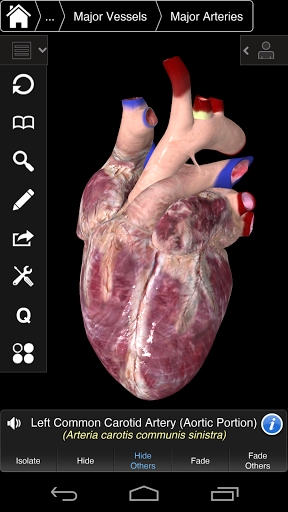

⁃все також включає в себе мозок і серце

---- Нова 3D-технологія за допомогою останнього графічного двигуна 3D4Medical

---- Більше 4000 дуже детальних анатомічних структур

---- Правильна аудіо вимова для кожної структури

---- Латинська номенклатура для кожної анатомічної структури